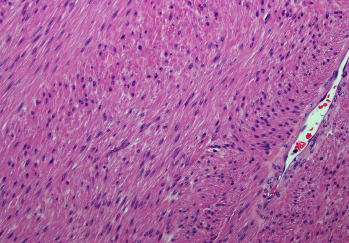

非胰岛细胞肿瘤性低血糖症(NICTH)是一种与大型间质肿瘤相关的罕见临床症状。其发病机制最常见的是肿瘤过量分泌 "大 "胰岛素样生长因子-2。在此,我们介绍一名 54 岁的男性患者,他出现了非胰岛素介导的低血糖症,腹腔内有一个 20 厘米长的子宫肌瘤。肿瘤切除后,他的低血糖症状缓解。据我们所知,这是英文文献中唯一一例男性患者伴有子宫肌瘤的 NICTH 病例。对于任何伴有低血糖和腹部肿块的患者,良性子宫肌瘤引起的 NICTH 都应列入鉴别诊断范围。

Non-islet cell tumor hypoglycemia (NICTH) is a rare clinical entity associated with large mesenchymal tumors. Its pathogenesis is most commonly mediated by tumor overproduction of "big" insulin-like growth factor-2. Here, we present a 54-year-old male who presented with noninsulin-mediated hypoglycemia and a 20 cm intra-abdominal leiomyoma. His hypoglycemic episodes resolved after the resection of his tumor. To our knowledge, this is the only documented case in the English literature of NICTH associated with leiomyoma in a male patient. NICTH due to a benign leiomyoma should be in the differential diagnosis for any patient with hypoglycemia and an abdominal mass.